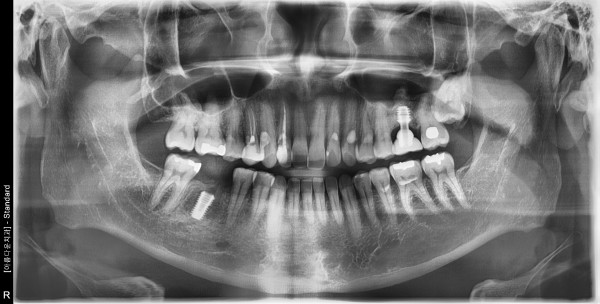

50대 남성 임플란트 식립